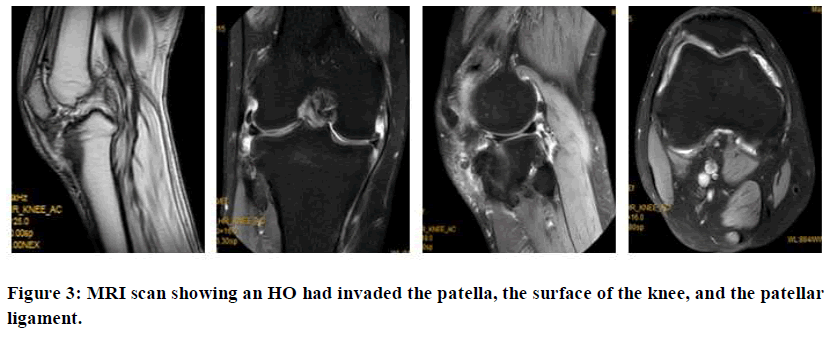

MRI examination results of the right knee showed readily visible thickening of the right patellar ligament and mixed signals, which increased with tibial tuberosity. There were also mixed signals of adjacent soft tissues. There was also proximal tibiofibular bone fusion, and hyperosteogeny at the edges of several bones. The cartilage beneath the articular surface was smooth.

Some effusion was found in the joint cavity and joint capsule. A strip-like hyper signal was seen in the meniscus, especially in the posterior corner of the medial meniscus, with swelling of the subcutaneous soft tissue (Figure 3).